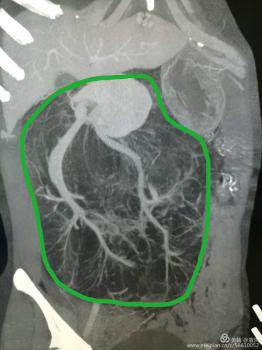

這一檢查讓婦科醫(yī)生也大吃一驚!醫(yī)生檢查時(shí)觸及腹部一硬質(zhì)包塊,無(wú)明顯邊界,上至劍突下,下至盆腔,兩側(cè)至腋中線,無(wú)壓痛,固定,說(shuō)明這包塊占據(jù)了患者整個(gè)腹腔,考慮來(lái)源于其它臟器,立即行全腹CT檢查??苫颊哂忻荛]空間綜合癥,一開(kāi)始拒絕CT檢查,醫(yī)生反復(fù)給患者做思想工作,并強(qiáng)調(diào)此項(xiàng)檢查的重要性,患者足足猶豫了兩天,才終于在醫(yī)護(hù)人員及家屬的鼓勵(lì)下順利完成了檢查。腹部CT提示,高度懷疑右腎有一顆脂肪肉瘤。

遂請(qǐng)泌尿外科會(huì)診協(xié)助診治,經(jīng)檢查,結(jié)合CT考慮腎周?chē)蚋鼓ず竽[瘤。最終診斷為:右腎巨大脂肪肉瘤。且腫瘤從腹腔延至盆腔,腹腔臟器受壓推移。醫(yī)生建議,子宮肌瘤多為良性,不影響生命,可暫緩手術(shù),但右腎巨大脂肪肉瘤必須盡快手術(shù)摘除。

經(jīng)血管重建提示:腫瘤供血豐富。泌尿外科建議:腫瘤來(lái)源于腎竇,手術(shù)風(fēng)險(xiǎn)極高。手術(shù)過(guò)程中,可能出現(xiàn)損傷動(dòng)脈出血,導(dǎo)致患者休克;取瘤后腹腔壓力下降,造成血壓下降,休克等風(fēng)險(xiǎn),術(shù)前須經(jīng)介入科行右腎血管栓塞治療。